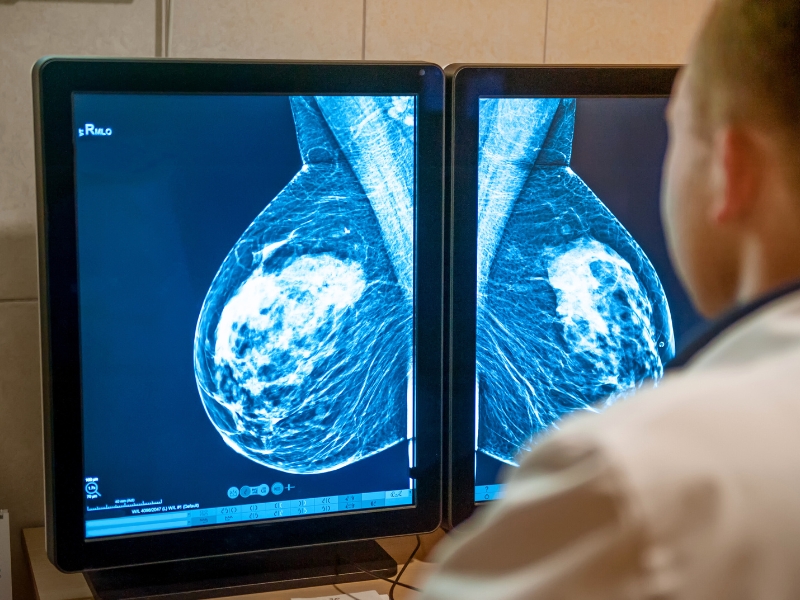

Você sabe onde fazer mamografia em Salvador? O câncer de mama é uma das principais preocupações de saúde feminina no Brasil, com dados do INCA apontando alta incidência na região Nordeste.

Dessa forma, a detecção precoce através da mamografia aumenta significativamente as chances de tratamento bem-sucedido, tornando essencial conhecer centros confiáveis em Salvador para realizar este exame preventivo regularmente.

Estudos indicam que o diagnóstico precoce através da mamografia regular pode aumentar as chances de cura do câncer de mama para até 95%. Nesse contexto, a ClivaleMais se destaca ao oferecer acesso à prevenção de qualidade e onde fazer mamografia em Salvador.

A clínica conta com equipamentos modernos que proporcionam imagens de alta resolução, essenciais para um diagnóstico preciso.